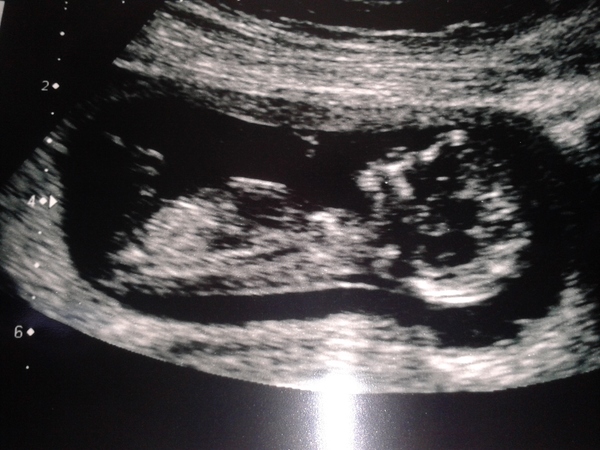

Thank you for your good wishes. No, not a good nights sleep but all in vain as I have a VERY active little baby! DH let you a high pitched giggle when it came on screen. Will try to add a pic. I'm so relieved, was convinced there'd be nothing there or something wrong.

Lovely pic Notta glad it went well ... You'll have a great night sleep tonight

Gingerbreadlady1 · 23/01/2015 15:18

Aw congrats notta, lovely picture.

Gorgeous pic notta, fantastic.

Congratulations Notta, great pic.

But congratulations notta! Whoop whoop, past the 12 week scan milestone!

Thank you everyone, its like finding out your pregnant all over again! I kept having these thoughts, that other than my own boots test, no one else had checked! What if it was all a big misunderstanding?!?! (conveniently forgetting the endless nausea and exhaustion....)

At last I feel able to start looking at cute baby stuff! Dh has def had a mindset change, he was being really good with how bad i have been feeling but seeing the baby on the screen today has really brought it home to him I think.

Ah lovely scan pic Notta! So sweet.